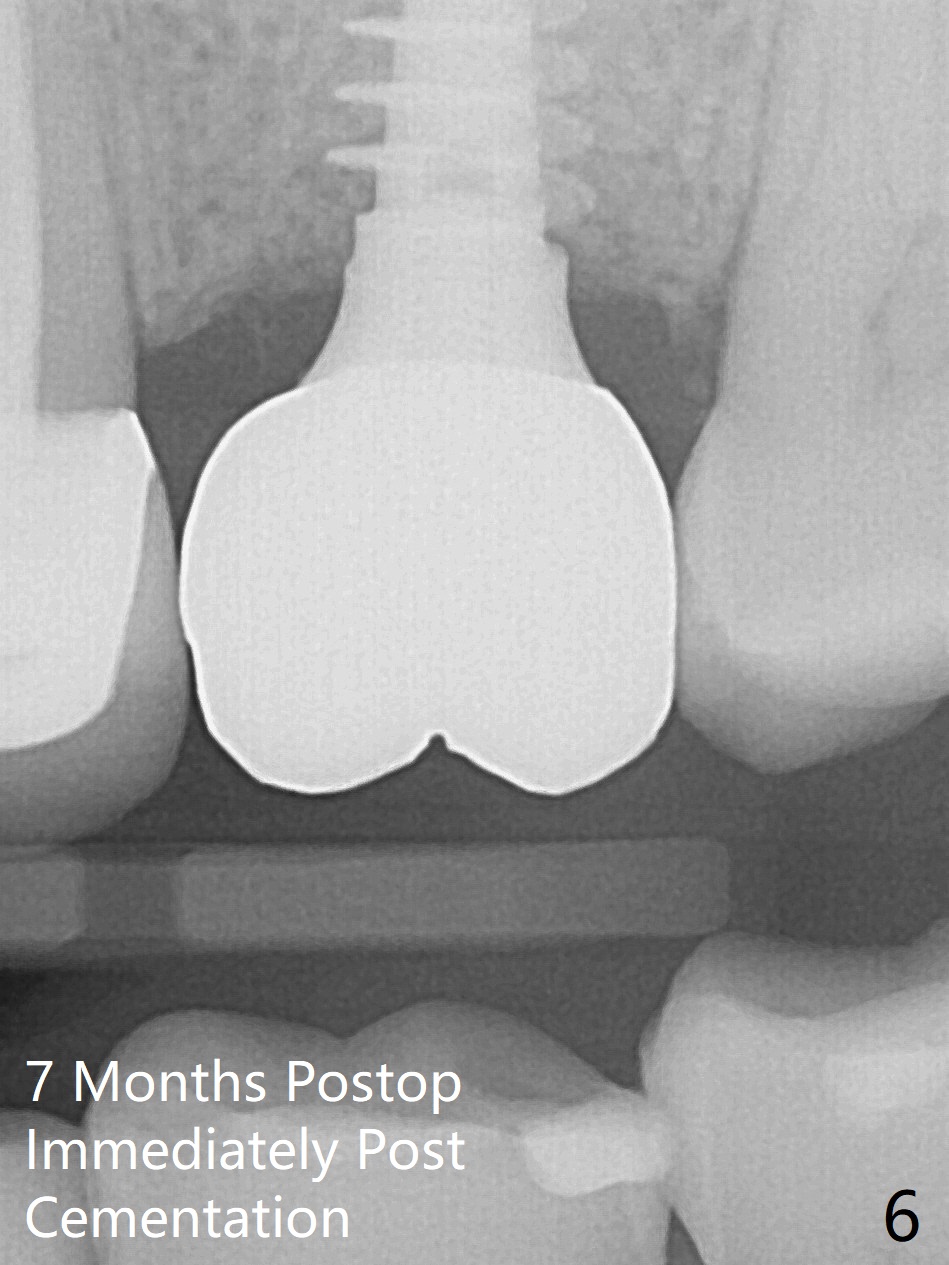

The ridge is wide at #14 11 months post socket preservation. Access and bone expansion (BEB) starts with Magic Split, followed by Magic Expanders 3.0, 3.8 and 4.3 mm from 8 to 9 mm for sinus lift. No bone is removed for osteotomy. Instead bone condensation occurs. After placement of a 4.5x11 mm dummy FC implant (Fig.1 with sinus lift (without bone graft)), a 5x9(2) mm Magicore (2 mm cuff) is placed with >55 Ncm with cuff margin at the gingival margin (Fig.2); a 5.5x3 mm solid abutment tries in. There is no occlusal clearance; trimming of the solid abutment will be needed. Later a healing screw is placed (Fig.3 *). There is no bone loss 5.5 months postop (Fig.4). A healing cap is placed without much tissue blanching. Instead a 5.5x3 mm solid abutment is placed; after height adjustment, impression is taken. A permanent crown is temporarily cemented 6 months postop (to rule out food impaction) and permanently re-cemented 7 months postop (Fig.5,6). CBCT taken 3-4 months post cementation shows that the implant threads are within the bone (Fig.7) and that the implant barely enters the sinus (Fig.8 *). That is significant since the patient has chronic sinusitis with thickened sinus membrane (Fig.9 *). The tooth #18 seems to have crazing line 10 months post cementation of the crown at #14 (overloading, Fig.10).